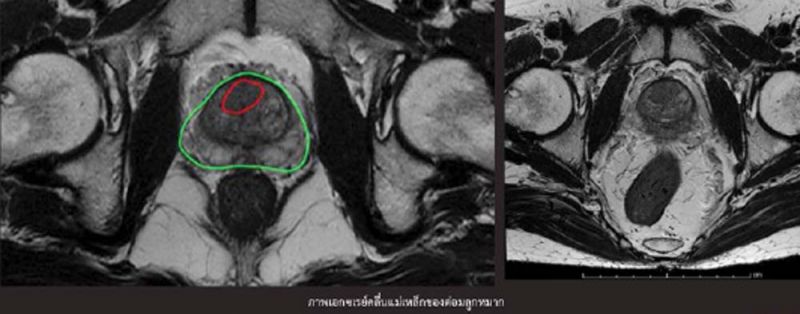

มะเร็งต่อมลูกหมากรู้ไวเพิ่มโอกาสหายขาด ด้วยเทคโนโลยีตัดชิ้นเนื้อโดยใช้ภาพเอกซเรย์คลื่นแม่เหล็ก

ด้วยเหตุผลดังกล่าวข้างต้น จึงมีการนำเอาเทคโนโลยีภาพเอกซเรย์คลื่นแม่เหล็กมาใช้ในการบ่งชี้ความผิดปกติของต่อมลูกหมาก รวมทั้งช่วยบอกความผิดปกติที่พบว่ามีแนวโน้มจะเป็นมะเร็งมากน้อยเพียงใด ซึ่งเมื่อได้ภาพเอกซเรย์คลื่นแม่เหล็กเรียบร้อยแล้ว แพทย์ก็จะนำเข็มเจาะเข้าไปยังบริเวณที่เกิดความผิดปกติของต่อมลูกหมากได้อย่างแม่นยำ เปรียบได้กับการมีแผนที่นำทางให้แพทย์หาตำแหน่งก้อนมะเร็งในต่อมลูกหมากได้สะดวกยิ่งขึ้น อาจกล่าวได้ว่าเป็นการใช้เทคโนโลยีการสร้างภาพ 3 มิติ พร้อมการทำอัลตราซาวนด์แบบ Real-time ช่วยให้แพทย์มองเห็นรายละเอียดและตำแหน่งของก้อนมะเร็งในต่อมลูกหมากได้อย่างชัดเจน ทำให้สามารถกำหนดบริเวณที่จะตัดชิ้นเนื้อออกมาตรวจวินิจฉัยได้อย่างแม่นยำโดยไม่ต้องใช้วิธีการสุ่มตัดแบบเดิมอีกต่อไป